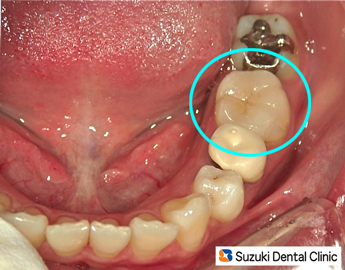

きれいなセラミックの詰め物=写真=が、装着されました。今後、セラミックの詰め物に何か問題が起こりましたら、当院が責任をもって対処しますので、気を使うことなく何でも噛んで下さいね。